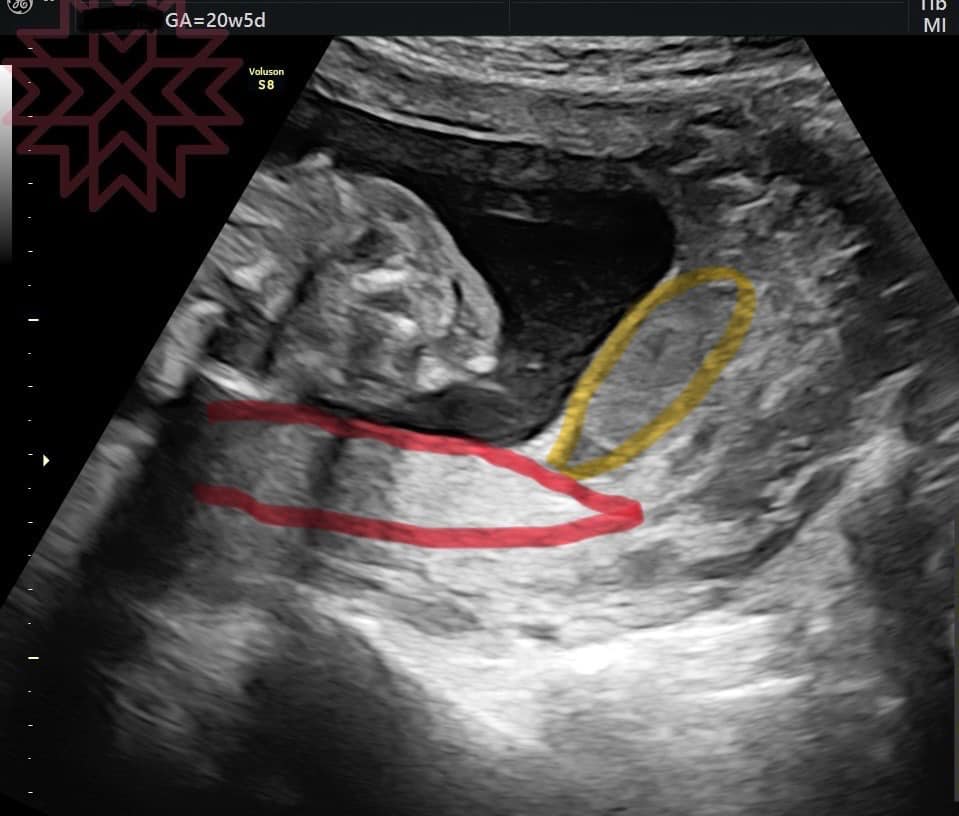

圖中

紅色圈起來的是胎盤

黃色圈起來的是血腫